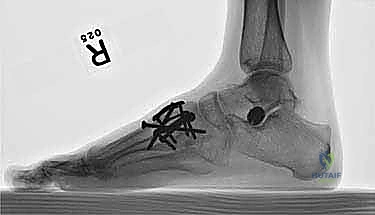

لضمان التحام العظام لتصبح عظمة واحدة صلبة، يجب تثبيتها بقوة هائلة حتى لا تتحرك أثناء فترة الشفاء. يتم استخدام مسامير معدنية متطورة (Screws)، أو شرائح معدنية خاصة (Plates)، أو دبابيس طبية متخصصة (Staples) مصنوعة من التيتانيوم الآمن على الجسم.

7. الإغلاق والضماد

بعد التأكد التام من وضع العظام وثباتها باستخدام جهاز الأشعة السينية داخل غرفة العمليات (C-Arm)، يتم إغلاق الشقوق الج